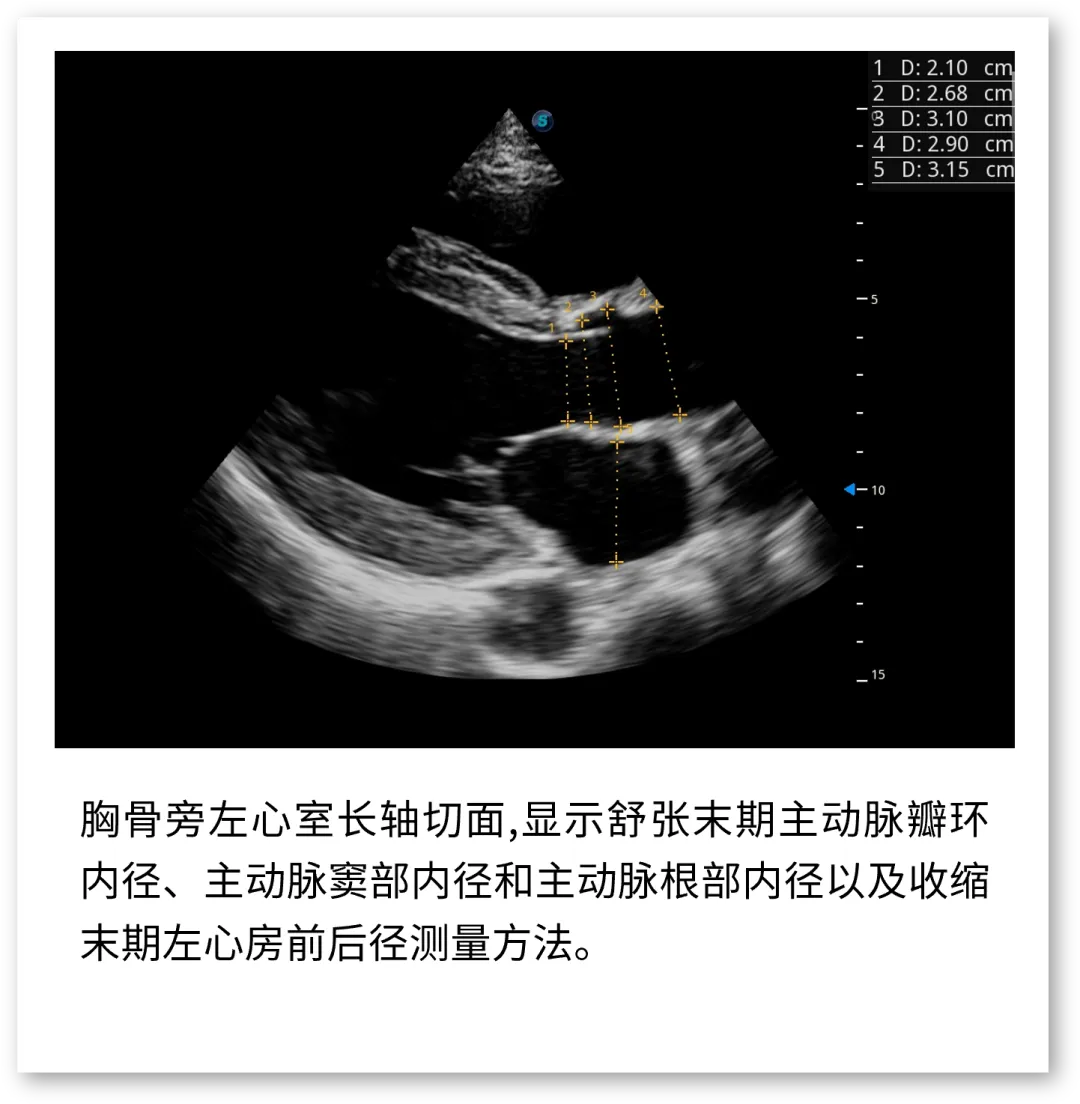

开立医疗联合武汉大学中南医院心血管病医院,将《心脏超声检查规范化中国专家共识 (2024版)》内容与实际临床工作需求融合,精心制作了指南挂图,助力标准采集,规范测量,期待这份实用且高清的工具,能成科室提升超声质效的助手!